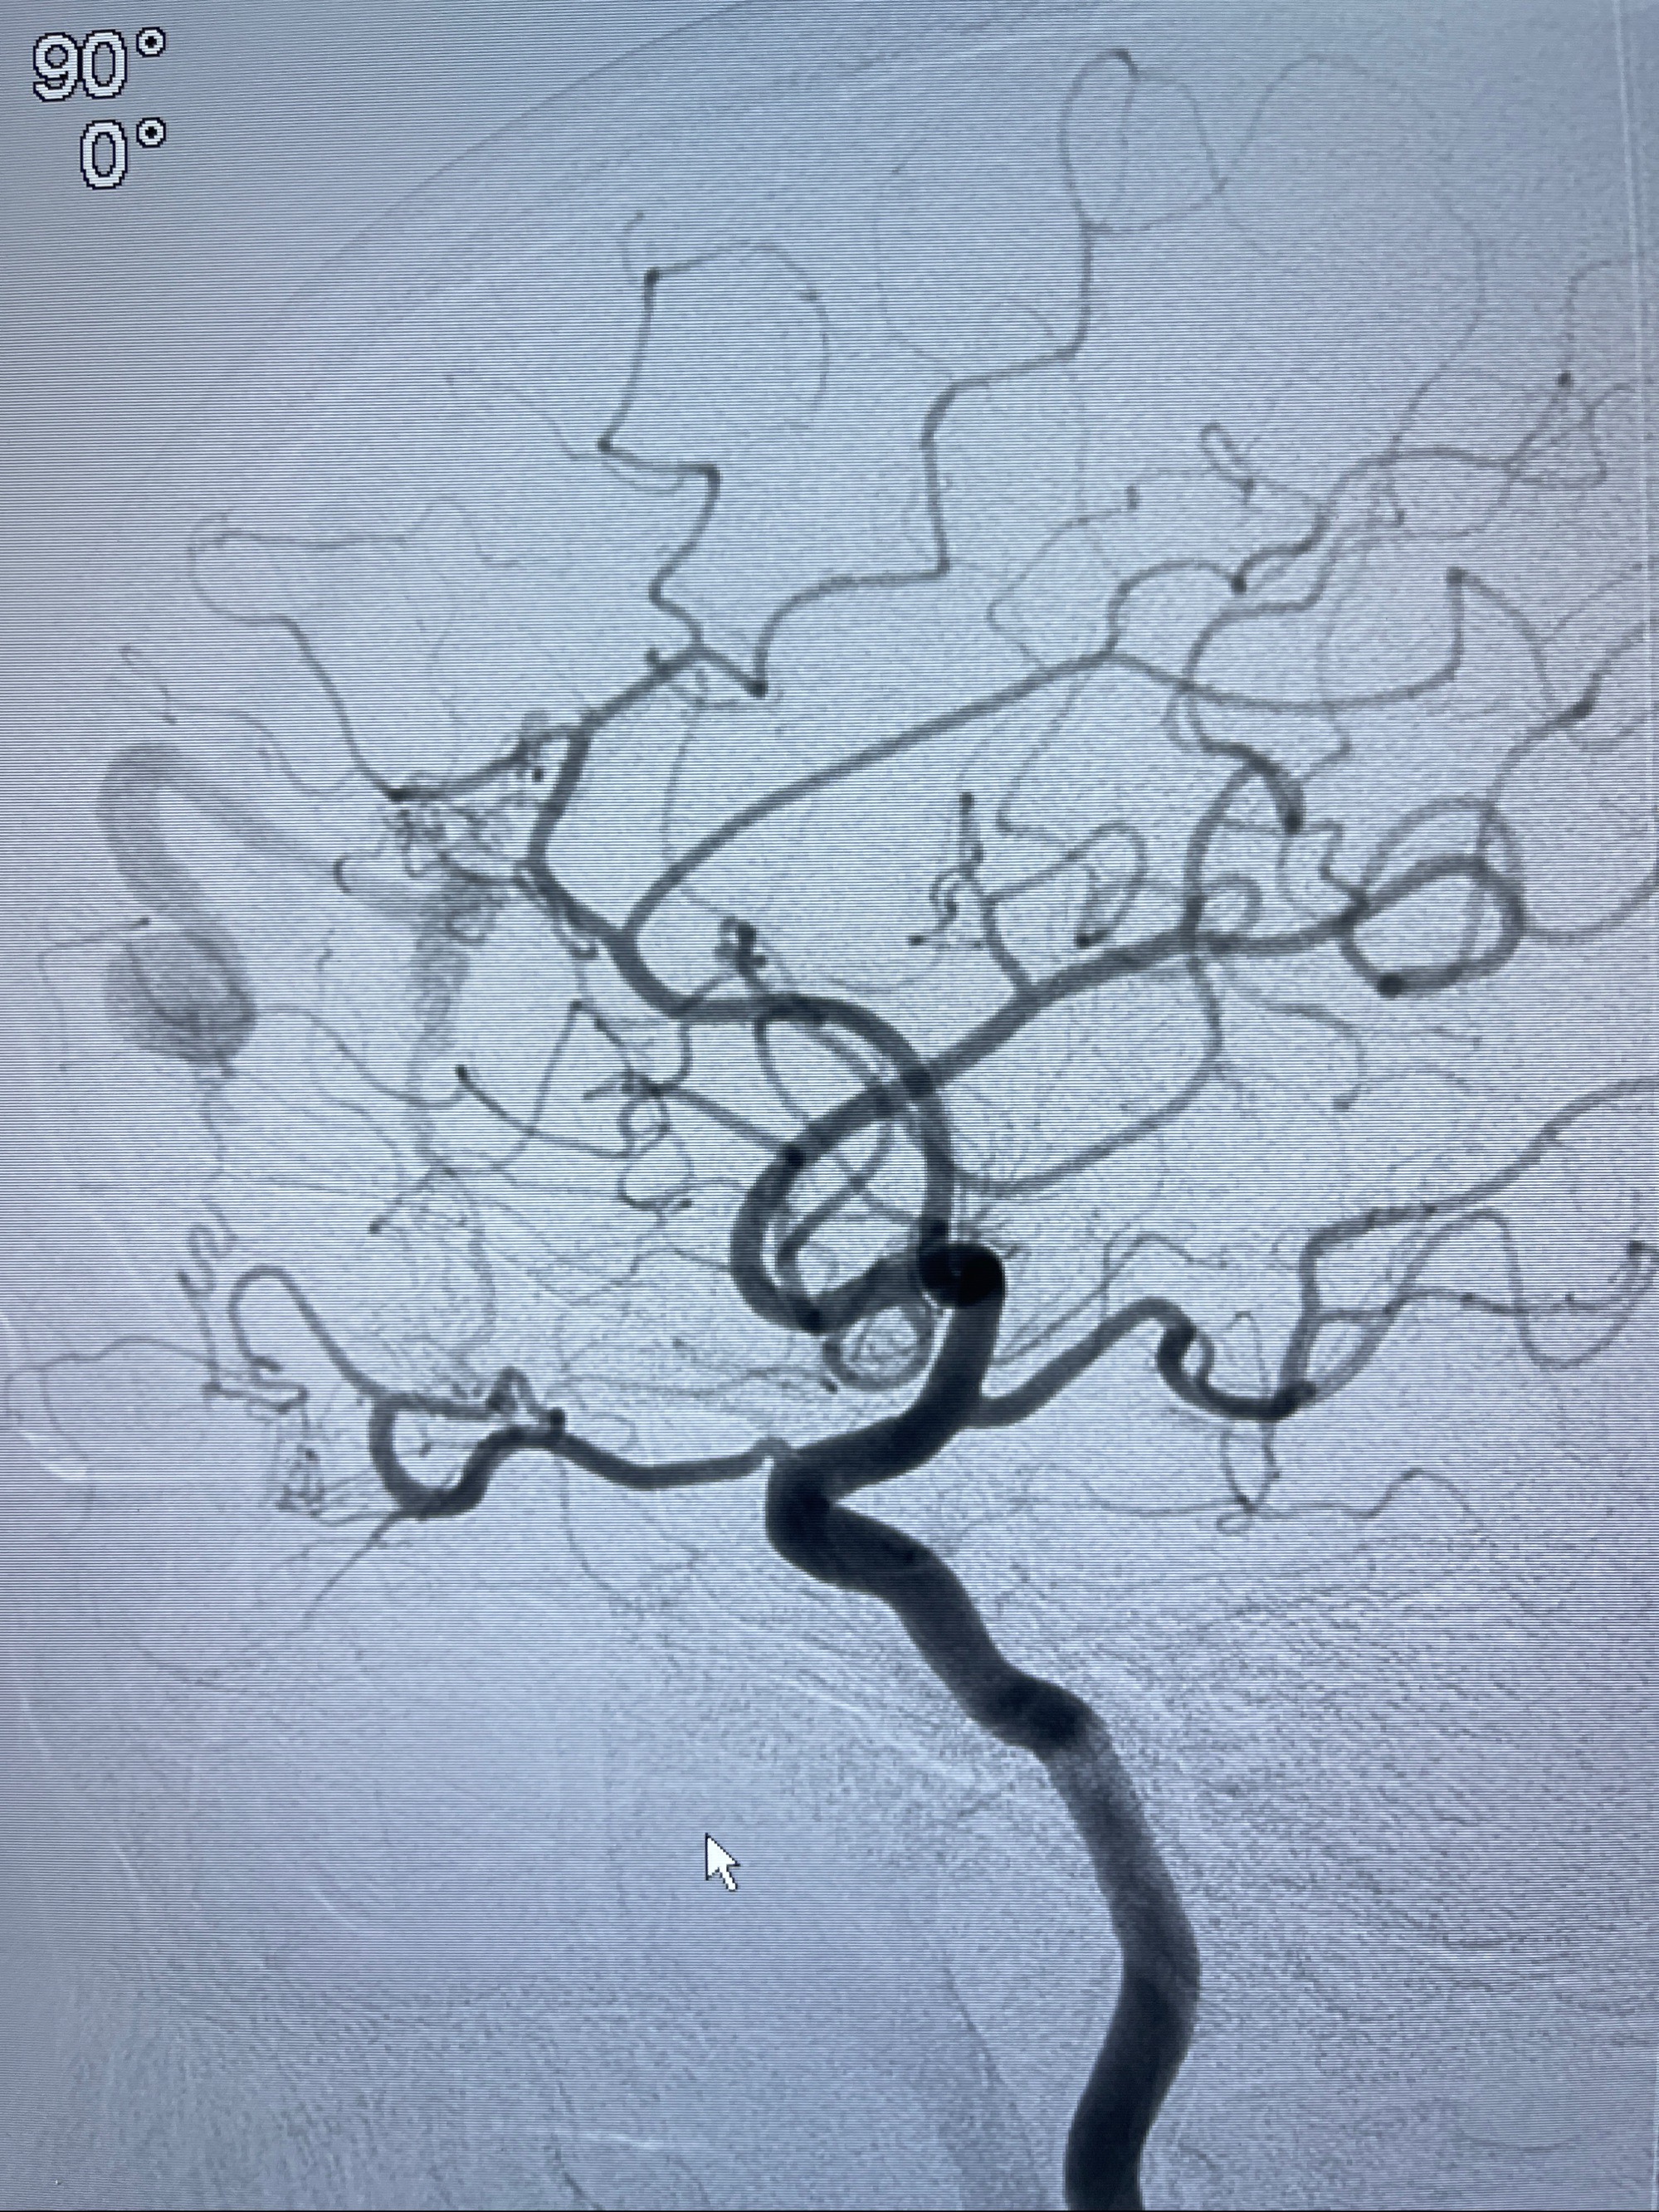

2023-09-13全脑血管造影:前颅底硬脑膜动静脉瘘,供血动脉为双侧胼周动脉、眼动脉脑膜支,静脉向上矢状窦方向引流